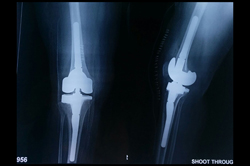

Total Knee Replacement - TKR